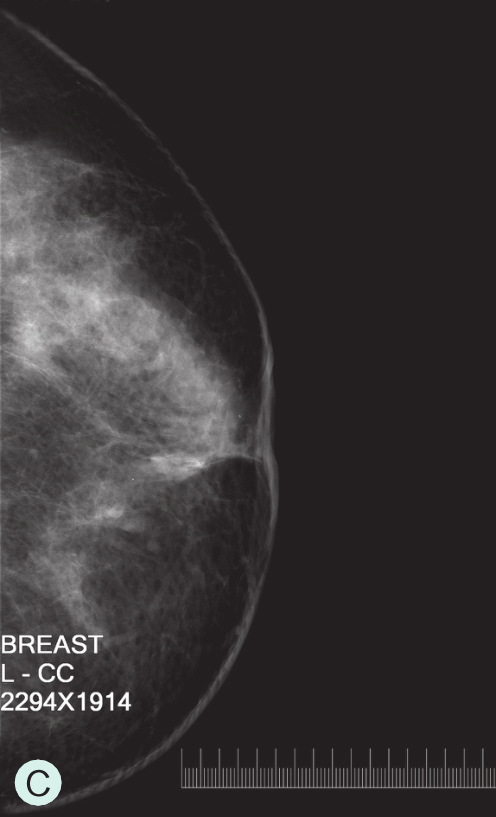

C级:不均匀致密型(可能掩盖小肿块)(图1-3-1C、图1-3-2C、图1-3-3C)。

图1-3-1 乳腺X线不同乳腺密度

A.脂肪型;B.散在致密型;C.不均匀致密型;D.极度致密型